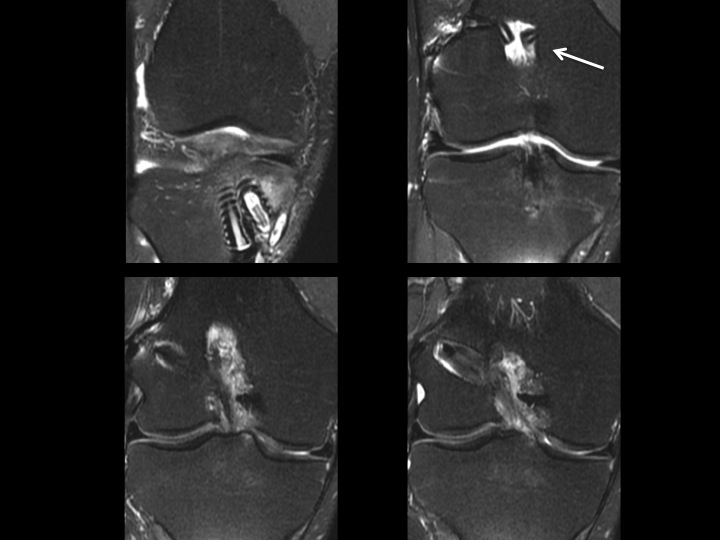

Figure 3 for case ACL graft device ( RID5523 )

Figure 3

There is fragmentation of one of the 2 bioabsorbable interference screws in the tibial tunnel, with a fragment situation in a cyst superficial to the tibial tunnel. The ACL graft is markedly attenuated. The last slide shows the failed, fragmented bioabsorbable femoral crosspin (arrow) from the initial reconstruction in 2011. Might be time for a Bone-Patellar Tendon-Bone autograft with metallic fixation?